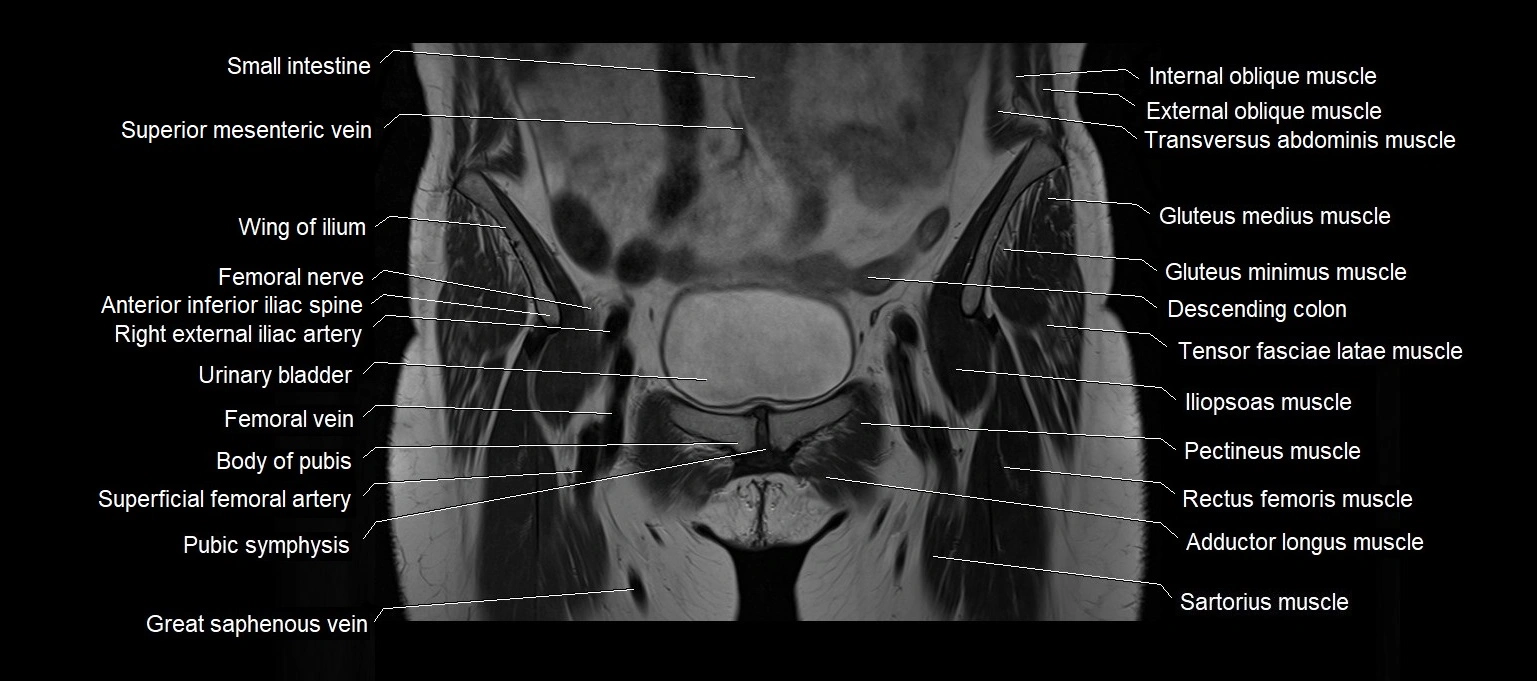

MRI images